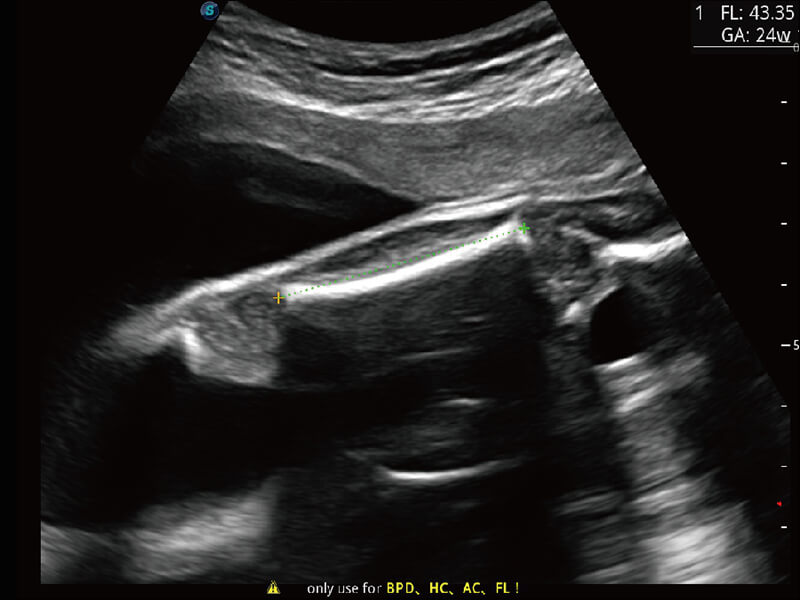

S60探头工艺,从前端信号处理每一个环节采集无损声学数据,真实还原组织原貌,再现解剖细节。

S-Fetus 产科扫查助手

• 缩短

操作时间

• 提升

准确率

• 单次

按键操作